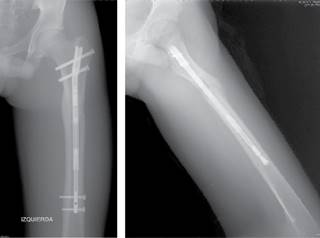

La consolidación ósea se observó en 100% de los pacientes con una media de tiempo de 113 ± 58 días. En dos casos se retiraron los clavos intramedulares después de un mínimo de un año de seguimiento según indica la técnica quirúrgica (Figura 6).